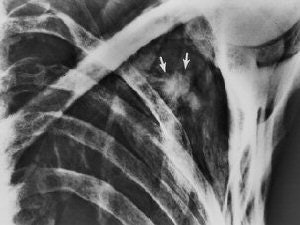

![]() |

| Transverse CT section (obtained on May 3, 1994) through the left shoulder region (caudal to the prehistoric arrowhead) shows an inhomogeneous area of attenuation (dehydrated hematoma, arrow) between the lateral rib cage and the scapula. Note the discontinuity in the ossified body of the scapula and the wispy soft-tissue opacity (hematoma) that extends through the bone defect (arrowheads). Authors speculate that the arrowhead and a portion of the arrow shaft penetrated the scapula in this location and that blood from the deep hematoma followed the arrow track into the subcutaneous tissues. Fig. 23, Murphy WA, zur Nedden D, Gostner P, et al. "The Iceman: Discovery and Imaging," Radiology 2003; 226:614-629. |